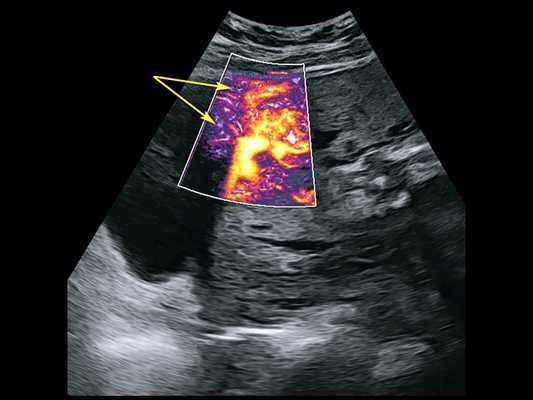

Сканирование в сроке 32 +4 нед беременности проводилось на ультразвуковом сканере премиум-класса W10 (компании Samsung) c использованием конвексного (CA1-7A) и внутриполостного (EV3-10B) датчиков с применением технологии LumiFlow™ (рис. 4-7).

Рис. 7. Беременность 32 +4 нед. Режим LumiFlow™: сосудистые мостики (rail sign) из миометрия сквозь серозный покров в стенку мочевого пузыря (стрелки).

В режиме серошкального сканирования все ранее идентифицированные особенности плацентации (PAS 3a): ретроплацентарные лакуны, васкулярная инвазия в шейку матки, исчезновение нормальной гипоэхогенной ретроплацентарной зоны, истончение миометрия, выпячивание плаценты, гиперваскуляризация пузырно-маточной зоны были подтверждены.

Дополнительное использование технологии стереоскопической визуализации кровотока (LumiFlow™) позволило визуализировать вовлеченность стенки мочевого пузыря беременной в конгломерат тканей аномальной плацентации (сосудистые мостики (rail sign) из миометрия сквозь серозный покров в стенку мочевого пузыря), то есть идентифицировать placenta percreta (PAS 3b). Проведенная в последующем МРТ констатировала полное предлежание плаценты с прорастанием в рубец, через все слои миометрия, шейку матки и цервикальный канал (рис. 8) и верхнюю стенку мочевого пузыря.

Учитывая определенную в итоге степень врастания плаценты как PAS 3b, беременность была завершена в сроке 36 +6 нед плановым родоразрешением. Была выполнена нижнесрединная лапаротомия с последующим донным кесаревым сечением, перевязкой внутренних подвздошных артерий, экстирпацией матки без придатков. В ходе операции при сепарации мочевого пузыря произошло его сквозное ранение с последующим послойным ушиванием. Особенности плацентации (глубокое прорастание с инвазией в мочевой пузырь и шейку матки), описанные при УЗИ, были верифицированы интраоперационно (рис. 9) и при последующем патологоанатомическом исследовании матки.

Таким образом, мнение E. Jauniaux и соавт., высказанное 6 лет назад [7], об отсутствии ультразвуковых признаков или их комбинации, специфичных для определения глубины инвазии плаценты, с внедрением в повседневную практику современных ультразвуковых технологий, LumiFlow™ в частности, может быть пересмотрено. Стереоскопическая визуализация кровотока, помогающая интуитивному пониманию структуры кровотока в мелких сосудах, является реальным инструментом в оценке степеней аномальной инвазии плаценты.